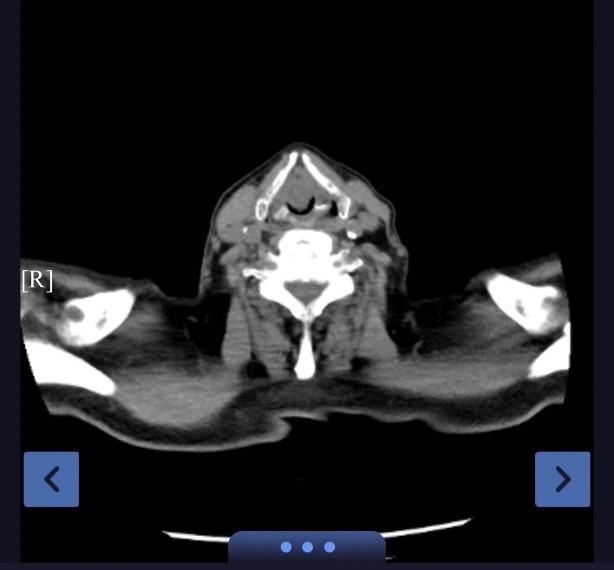

回溯病情,严老先生的求医之路充满波折。半年前,他无明显诱因出现声音嘶哑,在外院耳鼻喉科行喉镜检查未见异常,因而未引起足够重视。然而,病魔并未就此止步。1个月前,胸闷气急伴随着咳嗽咳痰症状悄然袭来,且在身体活动之后愈发严重。在外院接受住院抗感染治疗,病情却未得到有效控制。直至一周前,症状急剧恶化,夜间无法平卧,静息状态下不能耐受,短期体重下降15kg。患者及家属慕名来到苏大附四院蒋军红主任专家门诊,蒋主任凭借丰富的临床经验及精湛的医术,迅速判断出患者可能存在大气道狭窄,急诊完善颈胸CT证实了临床推断——巨大声门肿物伴大气道狭窄。

患者声门处的巨大肿物如同高悬的达摩克利斯之剑,随时可能引发呼吸困难,危及生命。蒋军红主任带领下的医疗团队迅速启动多学科协作机制,团队成员争分夺秒地推进术前准备工作,紧急邀请耳鼻喉科宋升桥主任医师、麻醉科李健主任医师协同开展联合诊疗。多学科专家凭借深厚的专业积淀,从患者心肺功能储备、肿物血运分布及毗邻组织关系、气道管理风险等多维度展开全面且精细的术前评估,围绕每一种可能出现的情况深入研讨,迅速且细致地做好气管切开准备,确保在关键时刻能够迅速、高效开展操作。并制定出一套精准而周密的治疗方案:首先选择喉罩全麻但需保留自主呼吸的情况下行支气管镜检查,切除一部分肿瘤组织,为气管插管奠定条件。

手术室内,气氛紧张而凝重。当支气管镜顺利进入,眼前的景象令人揪心:声门处管腔狭窄程度高达95%,巨大的白色肿物如同巨石般堵塞其中,表面光滑却质地坚硬。医疗团队沉着应对,先予圈套器多次圈套电切治疗,同时进行活检,样本送检常规病理。在精细操作下,声门得以部分暴露。在李健主任带领下的麻醉团队支持配合下,气管插管辅助通气。后续耳鼻喉科宋升桥主任凭借其深厚的专业功底,在支撑喉内镜下行喉部肿瘤等离子切除术。每一次操作都精准无误,每一个步骤都紧密衔接。在团队的共同努力下,肿物被逐步、分段切除,声带及喉室得以充分暴露,术后喉空间完全开放,管腔恢复通畅,如同被疏通的河道,重新恢复了生机,同时,凭借团队精湛的医术与充分完善的术前准备,避免气管切开带来的痛苦。术中患者生命体征始终保持稳定,术后患者呼吸明显顺畅,当晚便酣然入睡,目前患者正在住院恢复当中。